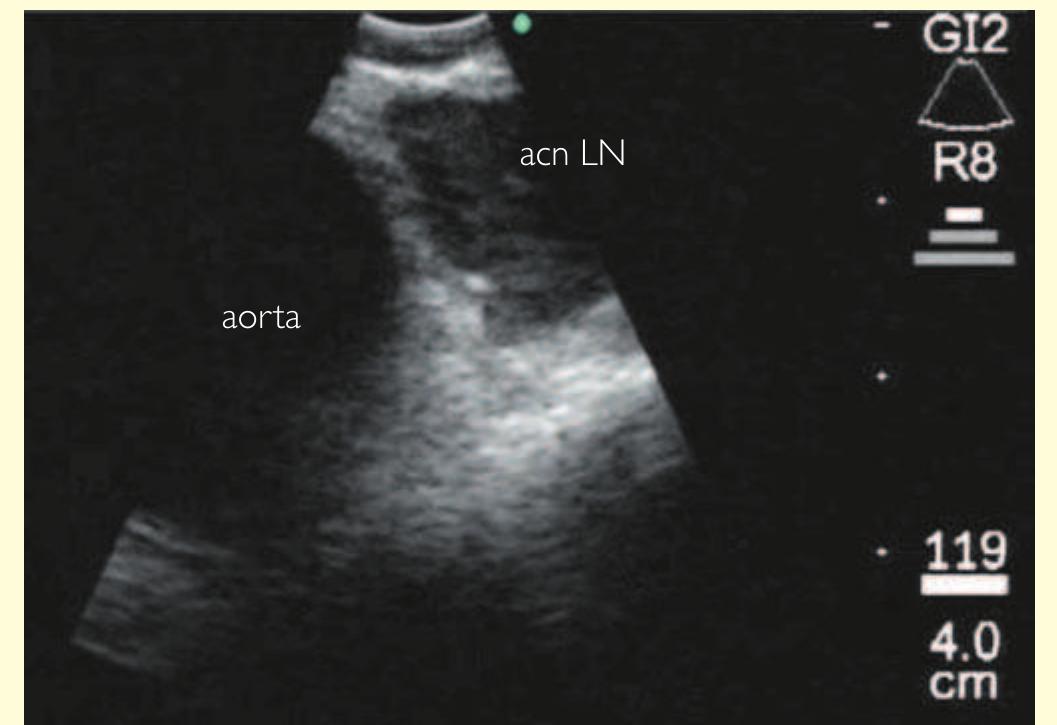

- The bronchoscope is then rotated anticlockwise by 150° to examine the subcarinal lymph nodes (station 7), extending down to the distal margin of the bronchus intermedius.

- Superior to the 11R lymph node, the right upper lobe bronchus and pulmonary artery may be visible.